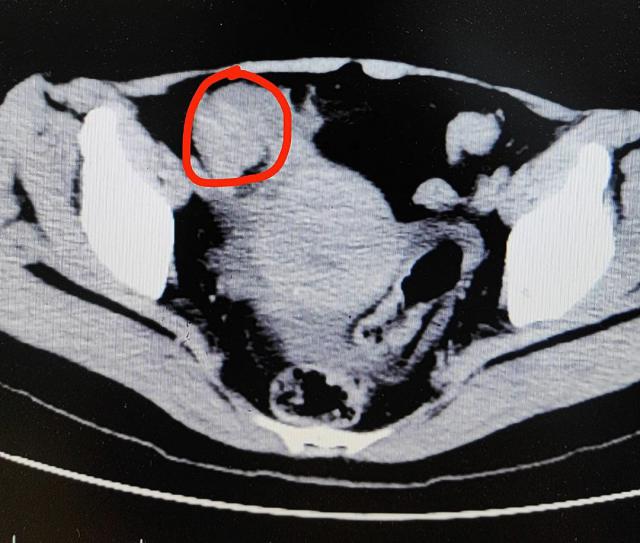

接受咨询的胃肠肛外科副主任医师尹光对冯女士进行了一系列检查,结果发现她的这种情况已经发生了小肠梗塞!

医师怀疑诊断,冯女士很有可能发生。绞窄性肠梗阻,腹腔镜检查和小肠取石术必须尽快进行。

手术证实,她的小肠里有许多硬结石,其中最大的一颗是4cm × 3cm,呈鸡蛋大小,肠道已被这块大结石顶得极度扩张,堵塞的肠腔周围出现淤血样变化。

由于肠道狭窄,异物无法通过,并出现缺血坏死。最终,大夫只能切除她 5cm 长出一条小肠。

如果柿子石比较小,可以通过肠道排出。冯女士体内的大柿子石终于经历了胃腔,但堵塞在肠道内,导致肠梗阻。